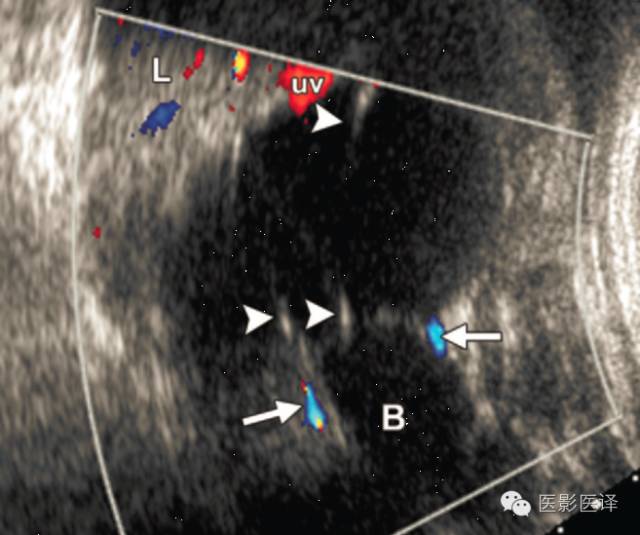

图4.多分隔卵巢囊肿。冠状位超声多普勒图像显示一个分界清楚的腹内囊肿,位于膀胱(B)上方及肝脏(L)下方,分隔较薄且壁无血管(箭头),双侧脐动脉(箭)是分辨胎儿膀胱的解剖标记。脐静脉(uv)在囊肿上缘上方进入肝内。